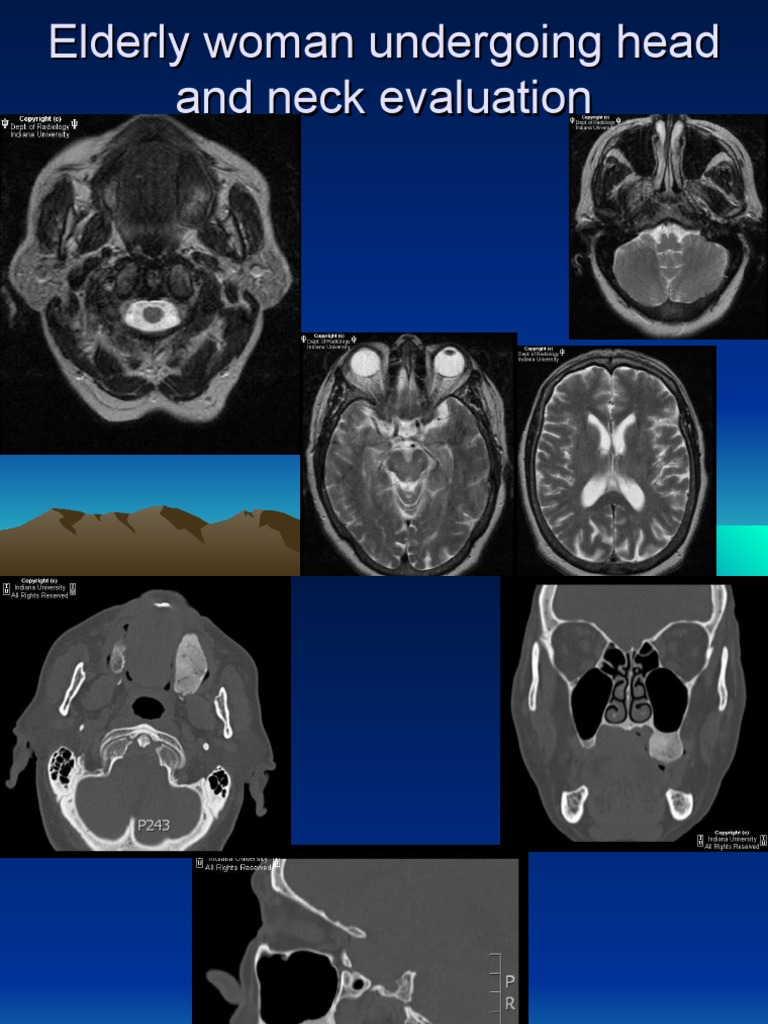

From www.slideserve.com

PPT Common Types of Radiology Scan and Tests PowerPoint Presentation What Is A Radiology Exam Medical doctors who specialize in radiology are called radiologists. 10k+ visitors in the past month Learn about department of radiology tests and procedures for people with serious, complex or rare health challenges. 10k+ visitors in the past month a radiologist is a medical doctor who specializes in diagnosing and treating conditions and injuries using. learn more about each. What Is A Radiology Exam.